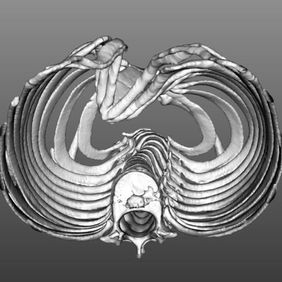

A severe depression is present in the center of the chest wall, with the right edge of the depression forming a ridge-like protrusion. Meanwhile, the edges and bottom of the depression have developed acute angle deformities.

We began by pre-shaping the depression to effectively release local stress and simplify the complex deformities. The Wung procedure and the Wang procedure were then simultaneously performed to correct the severe pectus excavatum and associated acute angle deformity. After the surgery, the chest wall deformity was completely resolved, and its appearance returned to normal.